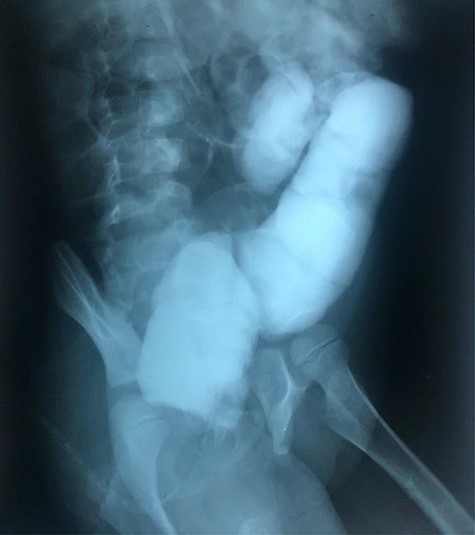

The clinical case consisted of a 4-year-old female patient who presented with long-standing constipation, which afflicted her since birth. The mother referred that the patient could only defecate 2 to 3 times per week, requiring the administration of rectal enemas, lactulose and plum juice. Upon physical examination, the patient presented increased frequency of intestinal sounds, no abdominal tenderness on palpation, tympanic sound to percussion, abdominal distention and a positive blast sign. A water-soluble contrast enema was performed to evaluate the colonic segments and rectum. The study displayed a distal narrow segment with proximal distention representing the pathognomonic transitional zone (Figs 1 and 2). Rectal biopsies were taken at 3, 5 and 10 cm from the anal margin. The biopsy at 3 cm showed hyperplasia of the muscularis mucosae and absence of the submucosal and myenteric nerve plexuses. However, the other two segments that were taken showed no abnormal findings. According to these findings, the patient was diagnosed with USHD. Treatment consisted of transanal myectomy of the internal anal sphincter.

Radiographic abdominal anteroposterior projection of water-soluble contrast enema.